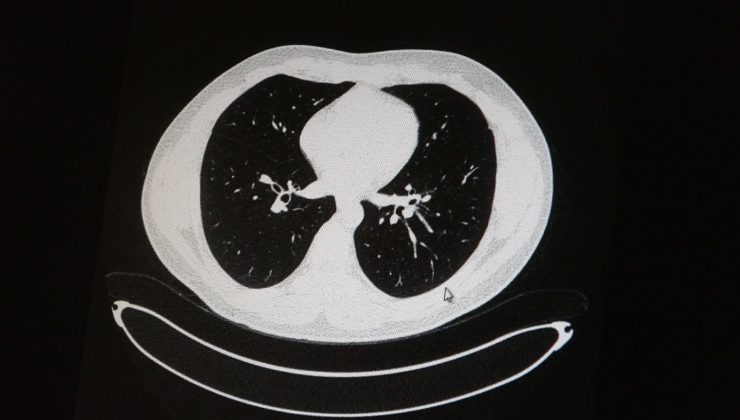

• Aşılı ve aşısız olarak koronaya yakalanan 2 gencin akciğer tomografisi korkunç gerçeği gözler önüne serdi

Aşılı ve aşısız olarak koronaya yakalanan 2 gencin akciğer tomografisi korkunç gerçeği gözler önüne serdi

Elazığ’da öksürük, halsizlik, yorgunluk ve çabuk yorulma gibi şikayetlerle hastaneye başvuran ve korona virüs tespit edilen 2 genç hastadan aşısız olanının tomografi sonuçlarında virüsün akciğerlerde zatürreye sebebiyet verdiği görüldü. Aynı şekilde aşı olup korona virüs hastalığına yakalanan bir başka genç hastanın bilgisayarlı akciğer tomografisinde akciğerinde herhangi bir sorunun olmadığı belirlendi.

Medical Park Elazığ Hastanesi Göğüs Hastalıkları Uzmanı Dr. Cebrail Azar, geçtiğimiz yıla oranla yoğun bakımda yatan hastaların yaş ortalamasının 65’ten 35’lere kadar düştüğüne dikkat çekti. Genç olduğu halde aşı olmayanlarda hastalığın ağır seyrettiğini ifade eden Uzm. Dr. Azar, “Ben gencim, benim bağışıklık sistemim kuvvetli” diyen genç bir hastanın akciğerlerinde ciddi lekelenmelerin olduğunu ve korona virüs zatürresi olduğunu gördüklerini belitti. Uzm. Dr. Azar, aynı şekilde aşı olup korona virüs hastalığına yakalanan bir başka genç hastanın akciğer tomografisinde akciğerde herhangi bir sorunun olmadığını ve hastanın durumunun iyi olduğunu gözlemlediklerini kaydetti. Uzm. Dr. Azar, sürekli şahit oldukları “Keşke biz aşı olsaydık” sözünü bir daha duymamak için herkesi aşı olmaya davet etti.